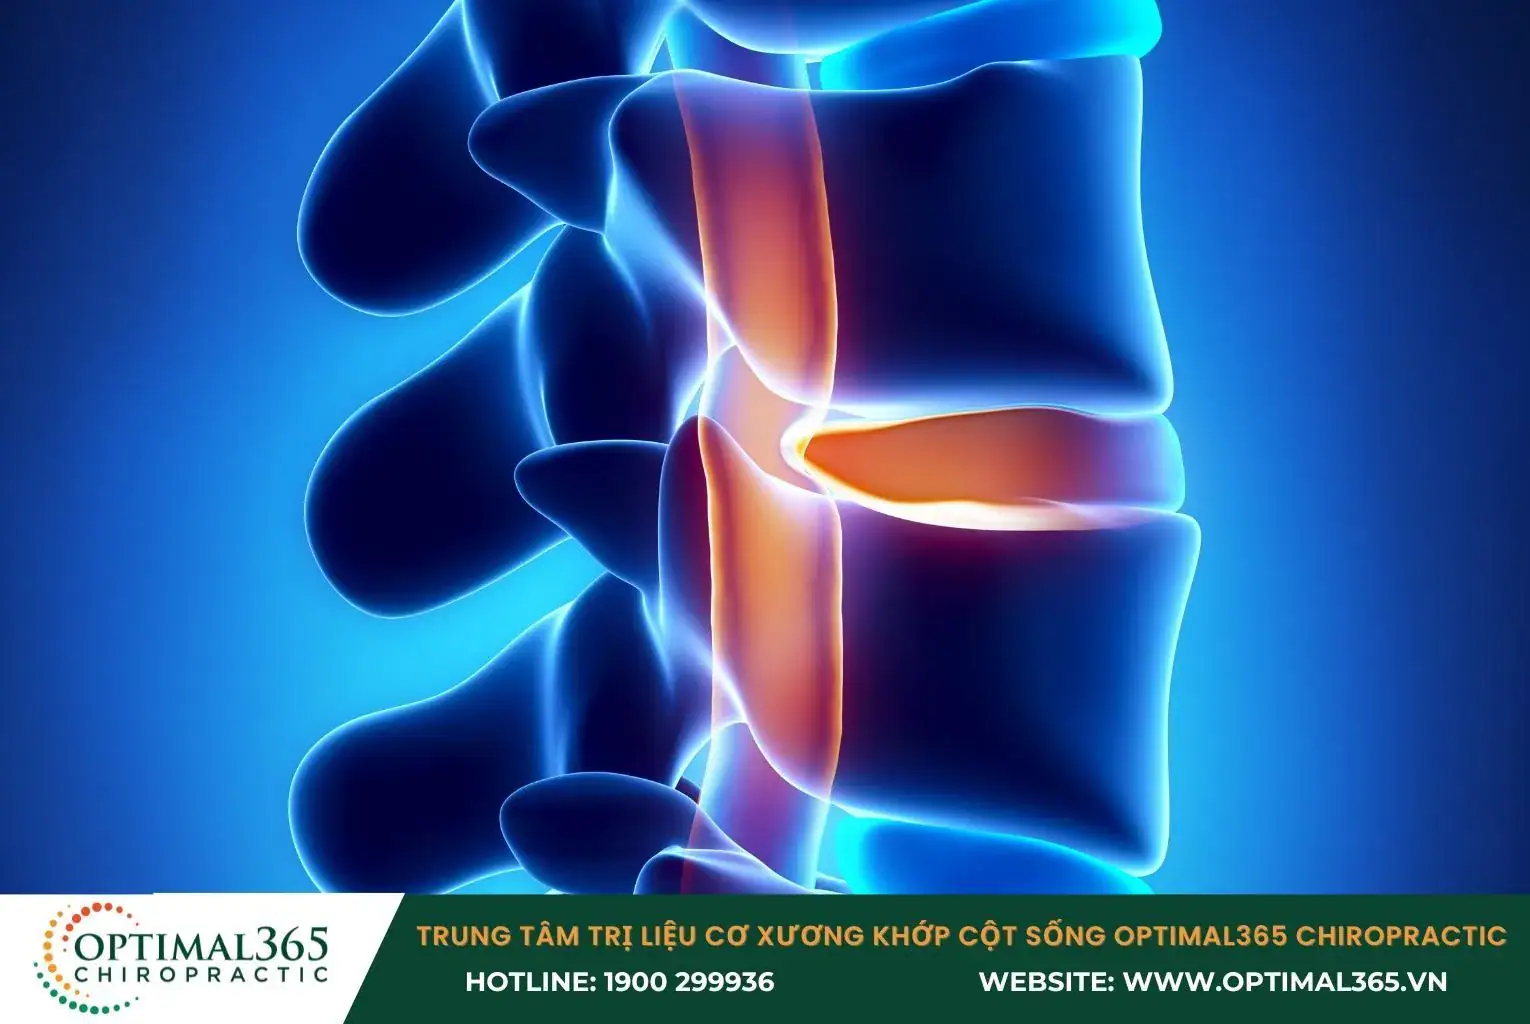

Về bản chất, ống sống là không gian bên trong của các lỗ sống trên các đốt sống, có chứa tủy sống và dây thần kinh. Từ tủy sống, các rễ dây thần kinh sẽ đi qua khe sống để chi phối các cơ quan trong cơ thể.

Hẹp ống sống là tình trạng thu hẹp chu vi làm giảm không gian bên trong ống sống, gây áp lực cho các cấu trúc thần kinh đi qua cột sống. Quá trình này có thể xảy ra bên trong ống tủy hoặc trong lỗ liên hợp đốt sống (nơi rễ thần kinh ra khỏi ống sống). Với mỗi vị trí và mức độ hẹp sẽ gây ra các triệu chứng khác nhau.

- Thoát vị đĩa đệm

Khi con người già đi, các đĩa đệm có thể bị khô và dẹt lại. Bao xơ bên ngoài xuất hiện vết nứt, khiến nhân nhầy bên trong tràn ra ngoài, hình thành khối thoát vị. Từ đó chèn ép lên các dây thần kinh gần đĩa đệm và có thể gây hẹp ống sống.